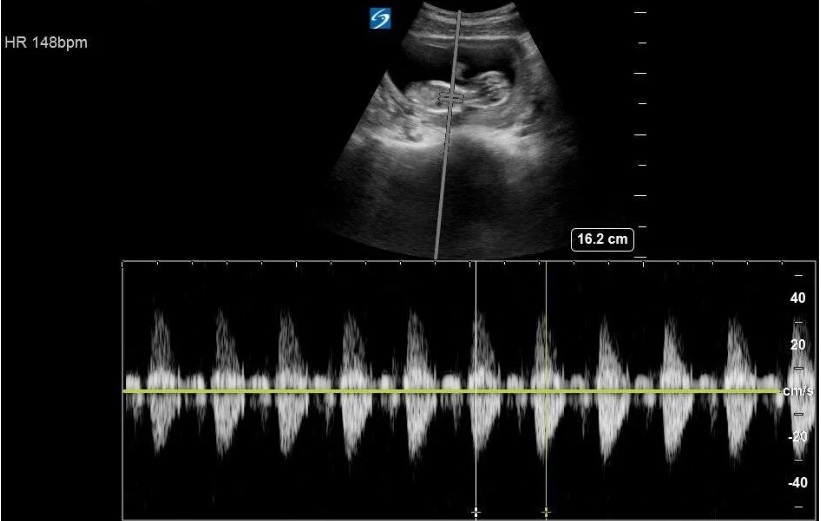

مد داپلر برای اندازهگیری و نمایش سرعت و جهت حرکت ذرات (مانند گلبولهای قرمز خون) به کار میرود. این روش بر اساس اثر داپلر عمل میکند، یعنی تغییر فرکانس موج بازتابی نسبت به فرکانس ارسالشده به علت حرکت ذرات.

سه نوع اصلی از مد داپلر وجود دارد:

۲. داپلر موج پالسی (PW Doppler) برای تعیین سرعت در عمقهای خاص،